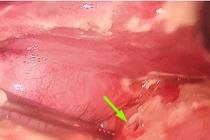

Chảy máu do loét dạ dày – tá tràng là một cấp cứu thường gặp, chiếm 40 – 45% trong chảy máu đường tiêu hóa trên. Bệnh thường gặp ở người trên 50 tuổi, có tiền sử loét dạ dày nhiều năm, chảy máu nhiều lần, gặp nhiều ở bệnh nhân có nhóm máu 0, thường xảy ra sau khi uống các loại thuốc giảm viêm không phải steroid như asipirin hay voltaren…hay sau khi dùng corticoid. Có những ổ loét chảy máu dữ dội nhưng có những ổ chảy ri rỉ có thể tự cầm…